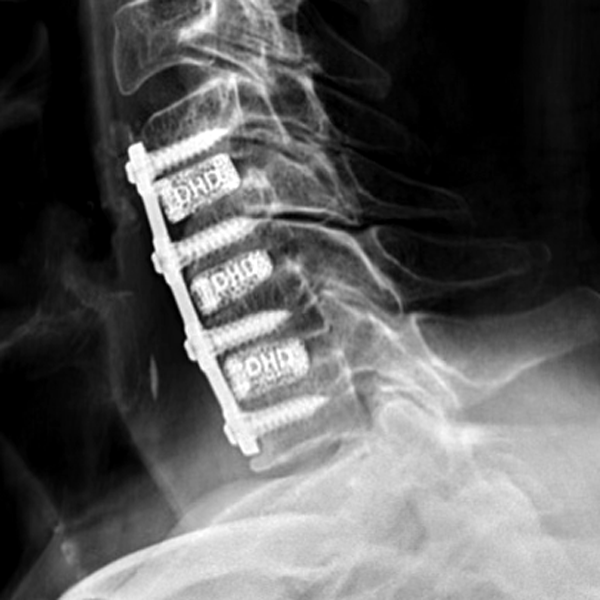

Frameless cervical cages made out of color-coded Titanium

Evolution of Cervical Spine Interbodies

3D Printed Cages

Too rigid

Subsidence issues

Endplate fractures